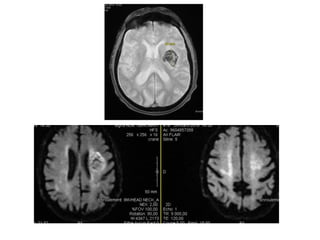

Mr A

• 82 ans

• Prothèse du genou gauche

• Pas de facteur de risque cardiovasculaire connu

• 29.03.2014 à 12h30 en présence de ses filles –

aphasie brutale et déviation de la bouche

• Aux urgences: aphasie globale, PF centrale

droite; NIHSS 11

• TA 183/82 mm Hg

• Loxen bolus i/v

• Objectif TA < 140/80 mm Hg

• Evolution favorable, persistance d’une

aphasie motrice sans trouble de la

compréhension

• Sorti en HAD MPR